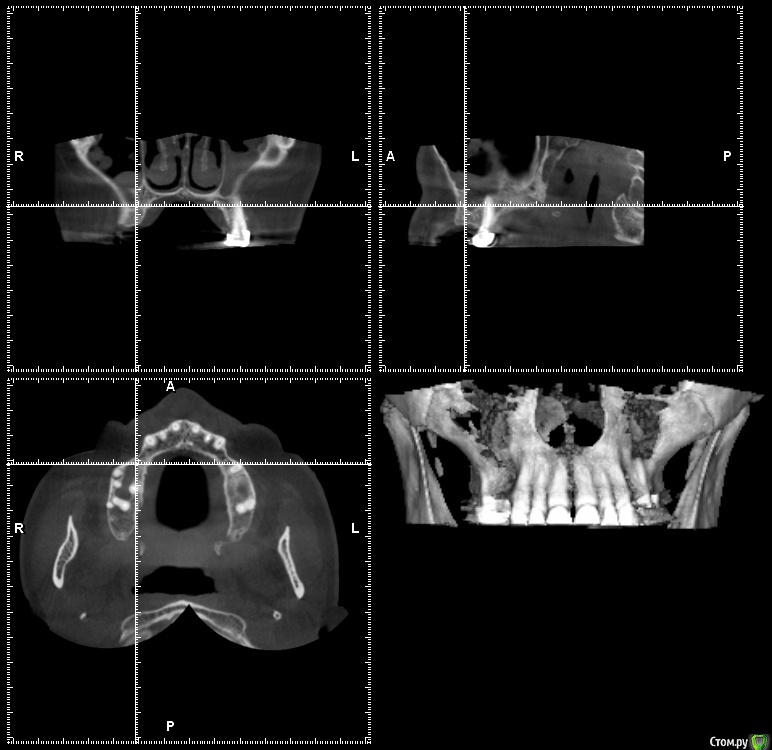

gum Опубликовано 28 сентября, 2015 Автор Поделиться Опубликовано 28 сентября, 2015 Пациентка принесла новый 3D. С пазухами. Слева сообщение с полостью носа есть, а справа по снимку оно не прослеживается.. Можно ли делать открытый синус лифт или к другому ЛОРу отправлять Ссылка на комментарий

Bier Опубликовано 28 сентября, 2015 Поделиться Опубликовано 28 сентября, 2015 а периодонтит? )Если кроме этого утолщения больше ничего нет - можно оперировать. 1 Ссылка на комментарий

major Опубликовано 28 сентября, 2015 Поделиться Опубликовано 28 сентября, 2015 лучше бы полное кт посмотреть. киньте ссылку. Ссылка на комментарий

gum Опубликовано 16 октября, 2015 Автор Поделиться Опубликовано 16 октября, 2015 Да периодонтит есть, пациентка пока в раздумьях Ссылка на комментарий